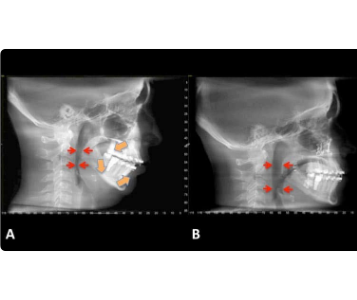

For children with smaller lower jaws, we use time-sensitive orthopedic appliances to guide the jaw forward into a more ideal position. This not only improves facial harmony but also lifts the hyoid bone, which supports the soft tissue airway — leading to better airflow and improved sleep quality.

3. 3D Growth Approach

Using 3D imaging and airway analysis, we can visualize the child’s airway, jaw structure, and growth direction. This allows for a comprehensive treatment plan that enhances both aesthetics and breathing function.

Before and After: Expanding the Airway, Expanding Possibilities

Our before-and-after cases clearly show the power of airway-driven orthodontics. After treatment, the palate is wider, the airway is larger, and the child experiences better sleep, improved focus, and enhanced overall wellness.